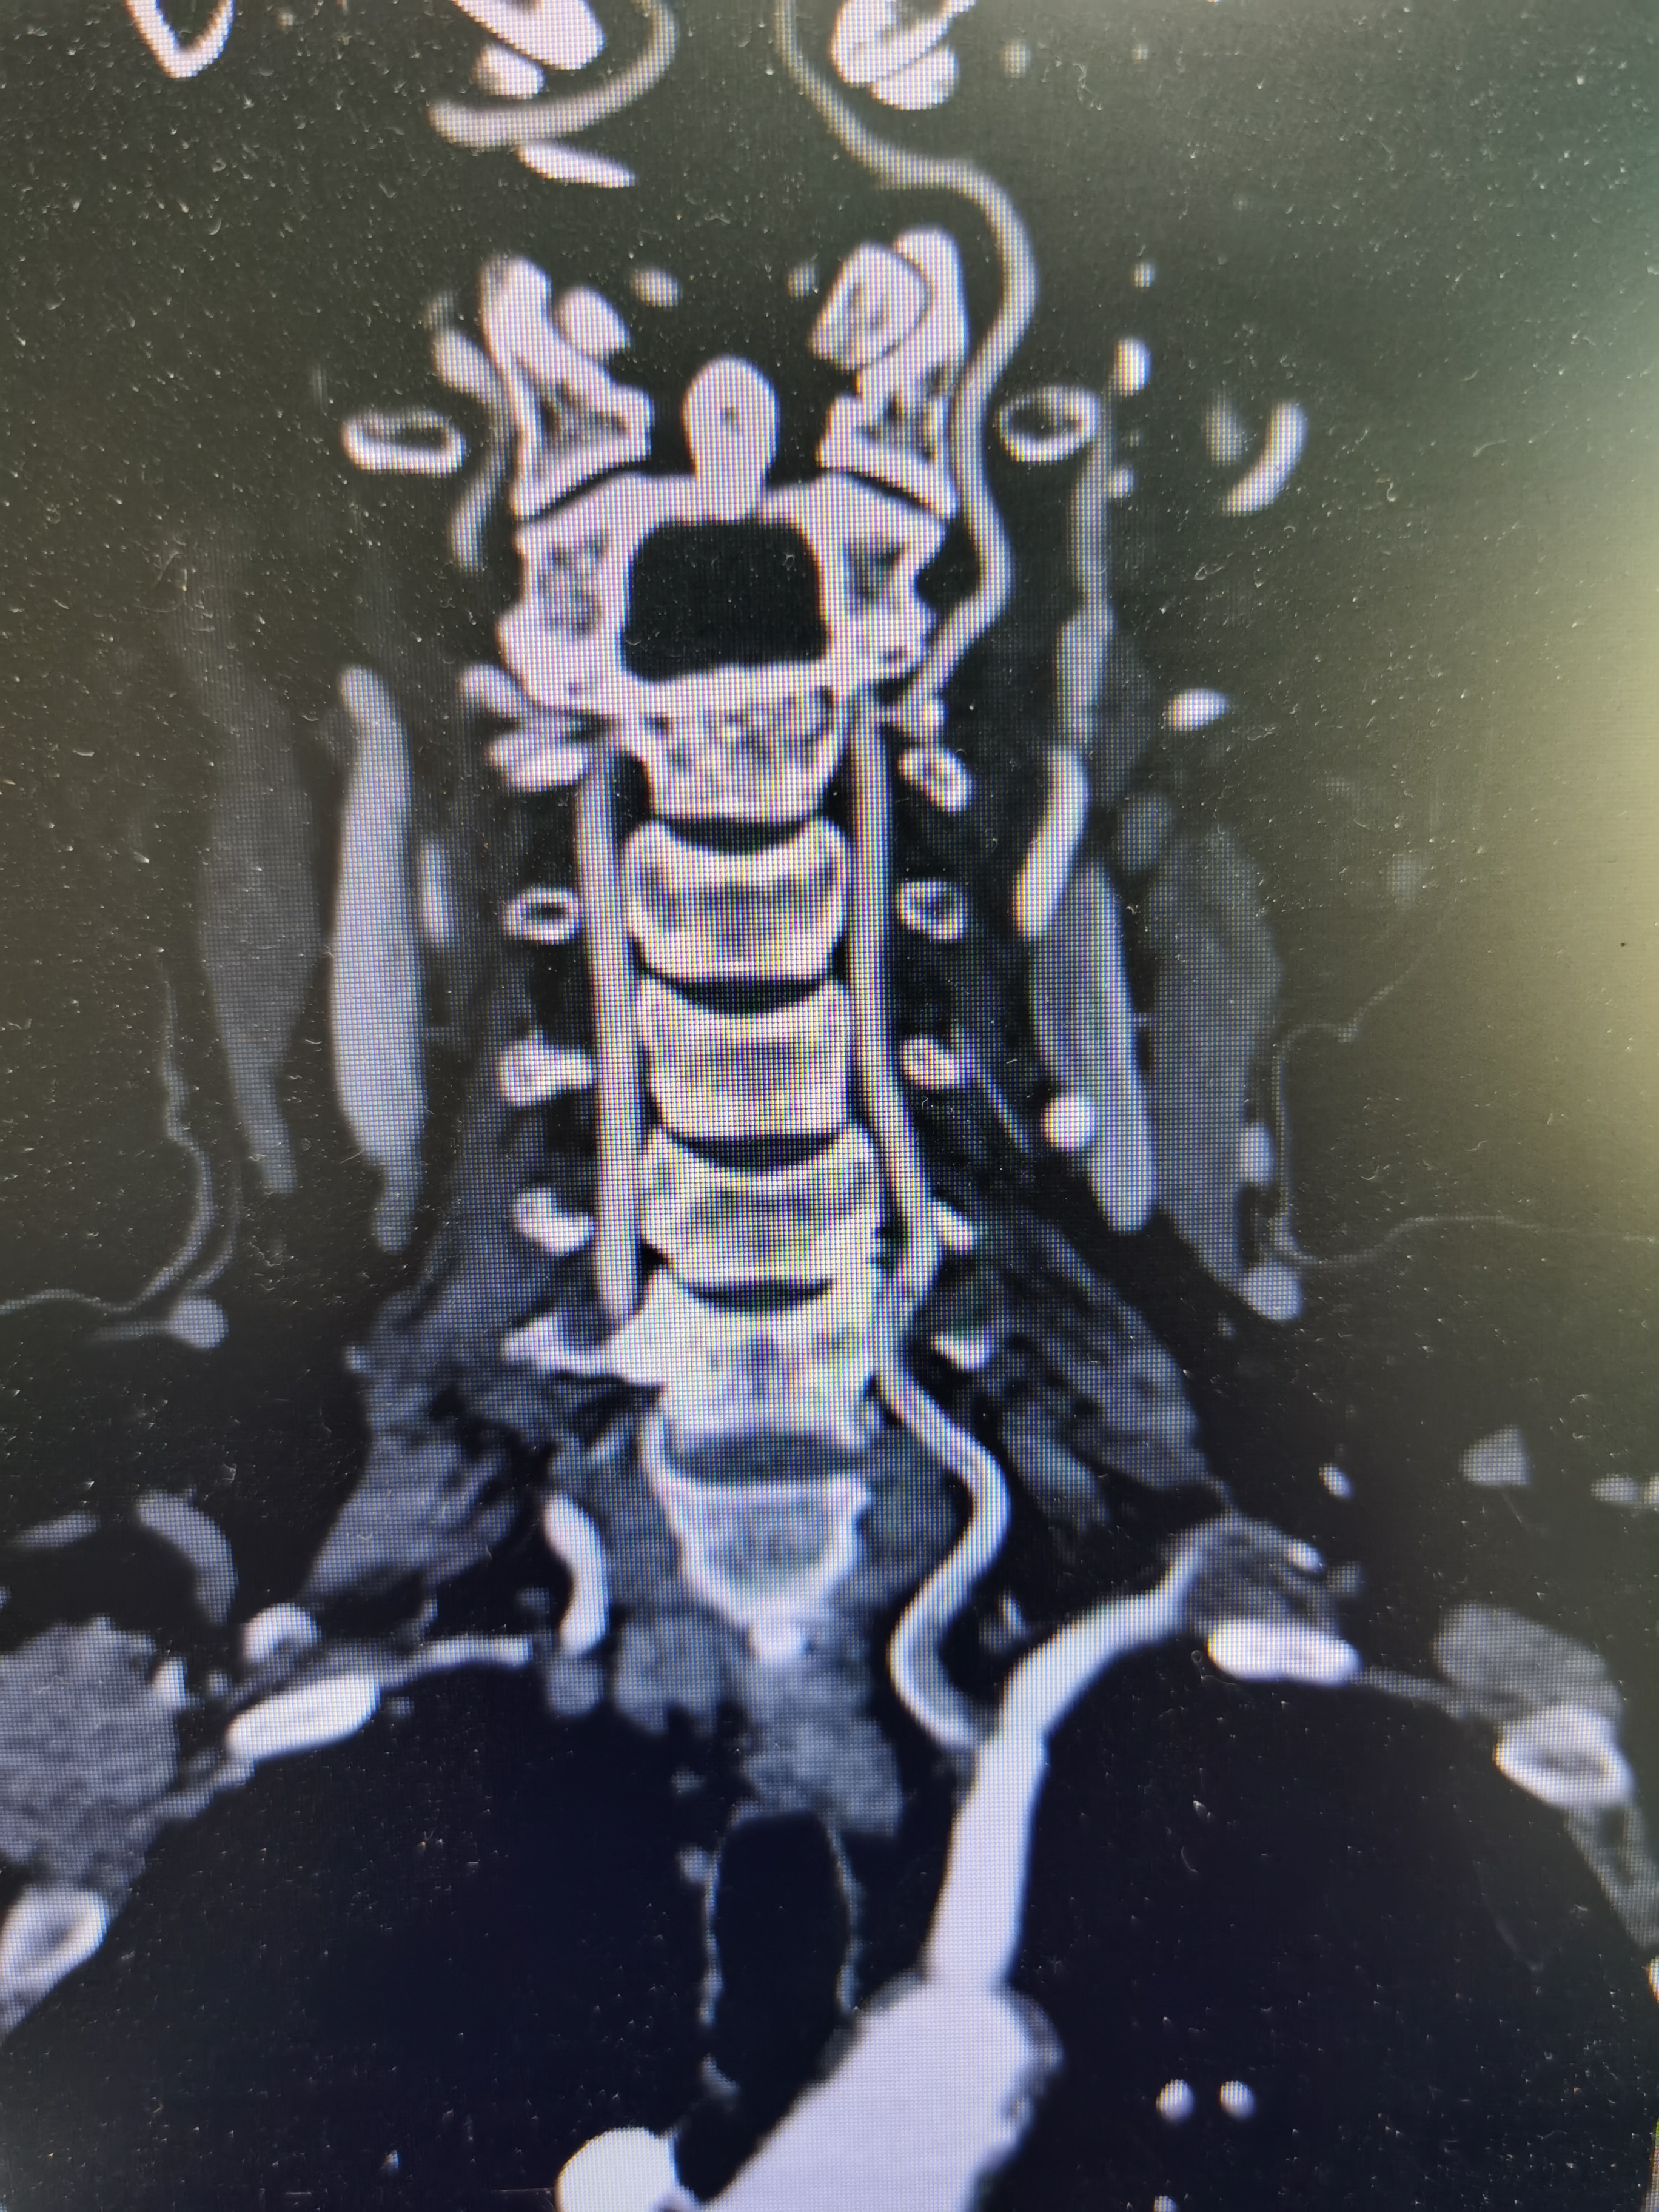

2、CTA证实左椎动脉起始部重度狭窄合并血栓,系责任血管,存在急性闭塞或残存血栓脱落至基底动脉风险,需积极处理。